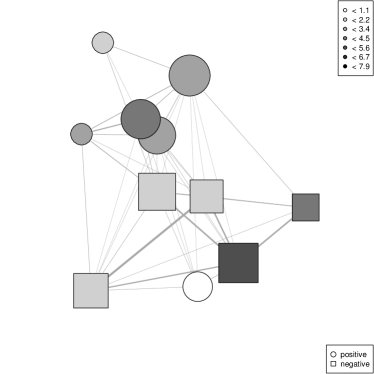

The classical strategy used to display a large network (e.g., with more than a hundred nodes) is to coarsen the network via a clustering method, leading to the so-called clustered graph visualization problem [4]. To implement this strategy, we use a maximal modularity graph clustering approach [12], as maximizing the modularity leads in general to meaningful clusters [5] which are additionally well adapted to visualization [11]. Then rather than displaying the original network, we use the standard Fruchterman Reingold algorithm [6] to display the network of clusters. Figure 2 gives concrete examples of the results: in the present context, each cluster consists of a group of patients linked by sexual relationships (the size of the group is represented by the surface of the disk used in the figures). Two groups are linked in the display when there is at least one sexual partnership between patients of the two groups. The thickness of the link encodes the number of between group sexual contacts.

We implemented the hierarchical principle used in [4] by providing interactive coarsening and refining of the clustering. Indeed the best clustering of the network might be too coarse to give insights on the structure of network or too fine to lead to a legible drawing. Coarsening is implemented by a greedy merging of clusters (as is used in [12]) while refinement is obtained by applying maximal modularity clustering to each sub-cluster, taken in isolation from the rest of the network. We keep only statistically significant coarsenings and refinements: the modularity of the selected clusterings must be higher than the maximal modularity obtained on random graphs with the same degree distribution (see [3] for details). Figure 2 (b) gives an example of a refinement for the clustering used in Figure 2 (a), while Figure 3 is based on a coarsening of the clustering.

Using [12], we obtain a partition of the giant component into 39 clusters, with a modularity of 0.85. This is significantly higher than the modularities of random graphs with identical sizes and degree distributions: the highest value among 50 random graphs is 0.74. The corresponding layout is given by Figure 2 (a). We use this layout as a support for visualization exploration of the sexual orientation distribution: nodes are darkened according to the value of a chi squared test conducted on the distribution of the sexual orientation of persons in each cluster versus the distribution of the same variable in the full connected component. It appears clearly that some clusters have a specific distribution of the sexual orientation variable.

The possibilities for refining the clustering in this case are quite limited: only 5 of the 39 clusters have a significant substructure. Nevertheless, Figure 2 (b), which shows the fully refined graph (with modularity 0.81) gives interesting insights on the underlying graph. For instance, an upper left gray cluster is split into 6 white clusters: while the best clustering of those persons leads to an atypical sexual orientation distribution, this is not the case of each sub-cluster. This directs the analyst to a detailed study of the corresponding persons: it turns out that the cluster consists mainly in MSM patients. Sub-clusters are small enough ( 7 patients) for MSM dominance to be possible by pure chance, while this is far less likely for the global cluster with 41 patients (among which 39 are MSM).

Coarsening can be done more aggressively on this graph: clusterings down to 8 clusters have modularity above the random level. With 11 clusters, the modularity reaches 0.81, a similar value as the maximally refined graph. While Figure 2 (a) is legible enough to allow direct analysis, the coarsening emphasizes the separation of the graph into two sparsely connected structures with mostly atypical sexual orientation distributions in the associated clusters, as shown in Figure 3 (a). Figure 3 (b) represents the Pearson’s residuals of the chi square tests for the MSM sexual orientation: it clearly shows that a part of the largest connected component contains more than expected MSM (circle nodes) while the other part contains less than expected (square nodes).

This finding directs the analyst to a sub-population study. The original 39 clusters are merged into three groups: MSM clusters (atypical clusters in the upper part of the graph which contain more MSM than expected), Mixed clusters (atypical clusters in the lower part of the graph, which contain less MSM than expected) and typical clusters. Then the geodesic analysis summarized in Table 2 is done at this group level, leading to Table 3.